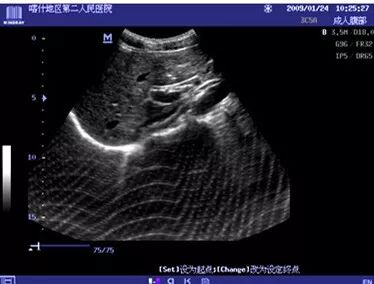

2、超声设备接收模块故障引起的干扰(DC-6)

现象:上图干扰会有规律的从左到右滚动

原因:模拟接收通道器件损坏

处理措施:更换放大板